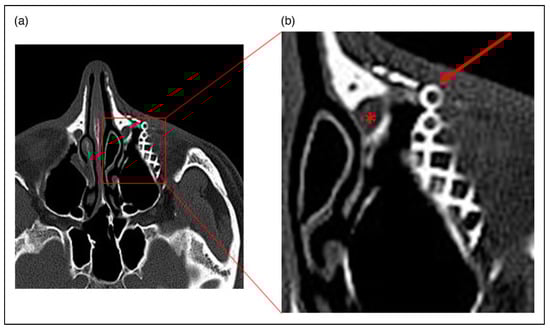

Case 2